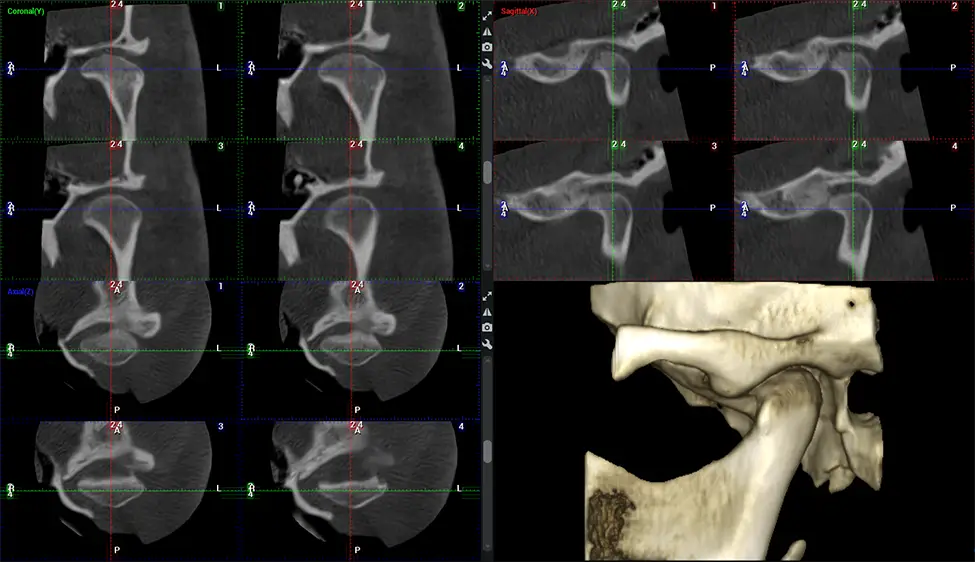

Cone Beam Computed Tomography (CBCT) is an advanced imaging technique used in dentistry and maxillofacial surgery to obtain detailed 3D images of the oral and maxillofacial structures. At Dr G Dental Studio, our CBCT scanners utilize a cone-shaped X-ray beam and a specialized detector to capture images from different angles. A computer then combines these images to create a 3D representation of the patient’s oral anatomy.

After the scanning process, the captured X-ray images are processed by the CBCT software, which applies algorithms to reconstruct a detailed 3D image of the scanned area. The software compiles these individual X-ray images and creates a digital 3D representation of the patient’s anatomy. The reconstructed 3D CBCT image can be viewed and analyzed by the dentist or radiologist. This image can be manipulated, rotated, and zoomed in or out to examine specific structures and evaluate the patient’s condition.

Upper Cervical Chiropractor Diagnosing structural problems in the C1-C2 vertebrae, assessing misalignment and instability, and evaluating chronic pain. Enables precise, weight-bearing views of the upper cervical spine, helping to identify abnormalities that inform targeted, non-invasive therapies.